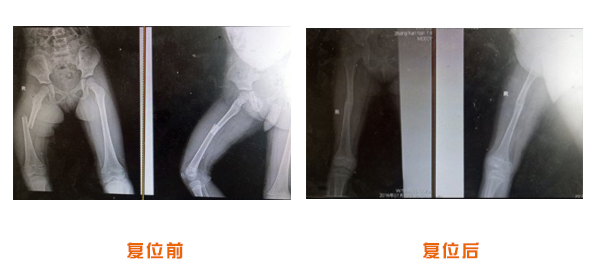

尺橈骨骨折治療前后

尺橈骨克雷氏骨折治療前后